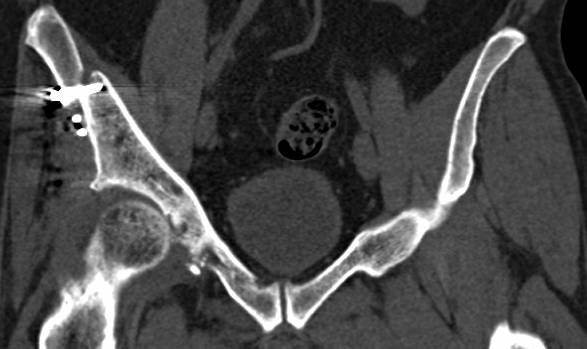

[Ortho] перелом правой половины таза

высылаю дополнительно  сканы.